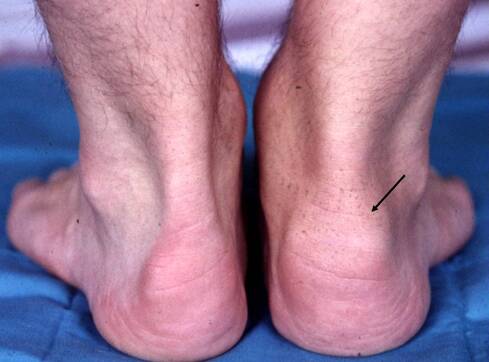

Ømme led

Det behøver ikke kun at være ryggen, der giver symptomer. Typisk kan det dreje sig om et hævet og ømt skulder-, hofte- eller knæled. Nogle oplever hælsmerter, som er værst om morgenen, men bedres op ad dagen. Dette kan skyldes irritation der, hvor akillessenen sidder fast på hælbenet

Fortykket hæl-tilhæftning af akillessenen på højre side.